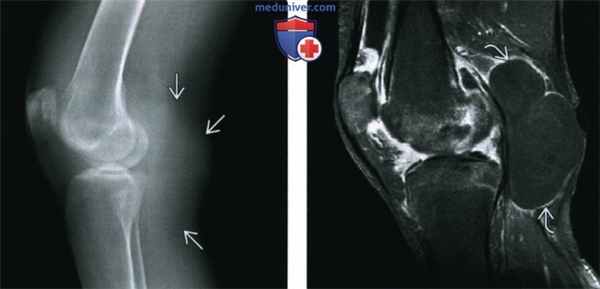

(Слева) МРТ, аксиальная проекция, режим Т1, с контрастным усилением, с подавлением сигнала от жира: контрастируемая утолщенная синовиальная оболочка с подтвержденным синовитом, что не является специфичным и может иметь место при септическом артрите. При анализе аспирата микроорганизмов или кристаллов обнаружено не было. Пациент был пролечен по поводу обострения РА и болевой синдром уменьшился.

(Справа) МРТ, сагиттальная проекция, режим протонной плотности: массивный выпот с многочисленными мелкими образованиями, соответствующими рисовым телам, которые наблюдаются при воспалительных заболеваниях суставов. Визуализируются признаки полной утраты хряща наряду с разрушением мениска.